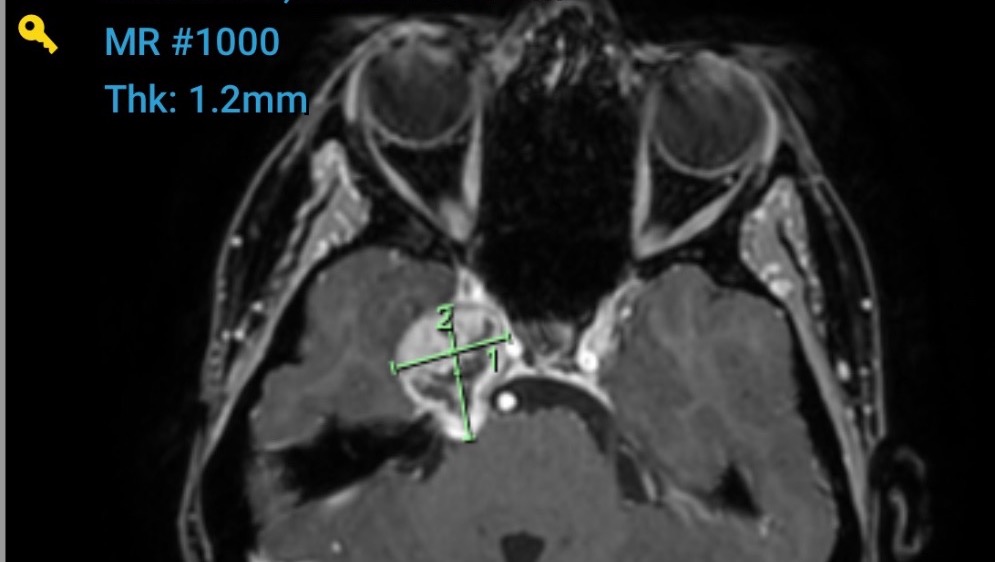

I found out I have Trigeminal Nerve Schwannoma for those who don’t know what this is, it’s a rare skull based Tumour. It’s located on my Trigeminal nerve causing debilitating Headaches, double vision and pins and needles on the right side of my face where my tumour is located. I am thankful & feel like I have won the lotto daily due to the fact that these types of tumours are mainly “benign” meaning they aren’t cancerous. It doesn’t take away how scared I feel, how anxious I am about everything medical, how my anxiety is through the roof, the panic attacks and I know that I have a long way of recovery not only mentally but physically with my road of recovery ahead.